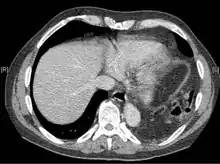

Axial lower chest CT scan showing bowel herniation due to left diaphragmatic rupture

A CT scan has an increased accuracy of diagnosis over X-ray,[7] but no specific findings on a CT scan exist to establish a diagnosis.[9] The free edge of a ruptured diaphragm may curl and become perpendicular to the chest wall, a sign known as a dangling diaphragm. A herniated organ may constrict at the location of a rupture, a sign known as the collar sign. If the liver herniates through a rupture on the right side, it may produce two signs known as the hump and band signs. The hump sign is a form of the collar sign on the right. The band sign is a bright line that intersects the liver. it is believed to result due to the ruptured diaphragm compressing.[13] Although CT scanning increases chances that diaphragmatic rupture will be diagnosed before surgery, the rate of diagnosis before surgery is still only 31–43.5%.[7] Another diagnostic method is laparotomy, but this misses diaphragmatic ruptures up to 15% of the time.[4] Often diaphragmatic injury is discovered during a laparotomy that was undertaken because of another abdominal injury.[4] Because laparotomies are more common in those with penetrating trauma than compared to those who experienced a blunt force injury, diaphragmatic rupture is found more often in these people.[14] Thoracoscopy is more reliable in detecting diaphragmatic tears than laparotomy and is especially useful when chronic diaphragmatic hernia is suspected.[4]